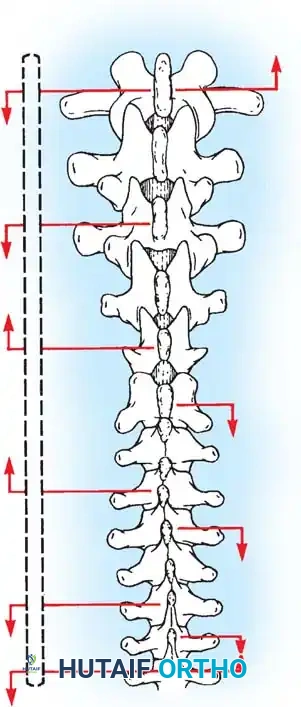

Biomechanics of Bone Grafting

Bone graft incorporates most effectively under compressive loads and is biologically disadvantaged in environments of distraction. Therefore, in scoliosis correction, if autogenous bone is limited, it should be preferentially concentrated on the concave side of the curve, which is subjected to compressive forces, rather than the convex side, which experiences tension. Furthermore, the farther the fusion mass is placed from the instantaneous axis of rotation, the more effectively it will neutralize movement across that axis.